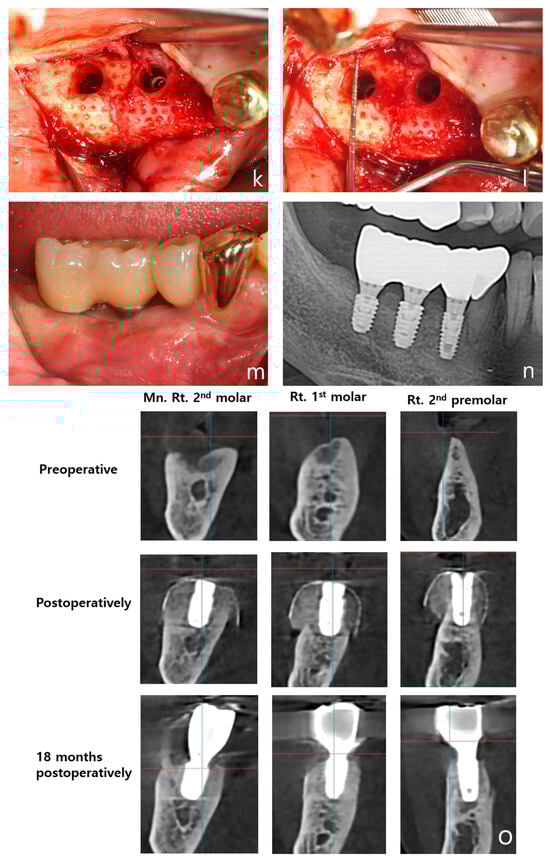

- Clinical efficacy: the combination of rhBMP-2 and a 3D-preformed titanium mesh (3D-PFTM) proved effective for reconstructing severely resorbed alveolar bone;

- Osteoinductive potential: rhBMP-2 demonstrated strong osteoinductive activity, even in patients with compromised bone regenerative capacity;

- Structural stability: the use of 3D-PFTM, particularly the OssBuilder system, provided reliable structural support for bone regeneration;

- Implant success: the combined approach resulted in stable bone regeneration and long-term implant success;

- Therapeutic value: the so called BOXAM (BMP-2, Oss-builder, xenograft, allograft, maintenance) technique appears to be a promising and reproducible strategy in dental and maxillofacial surgery.